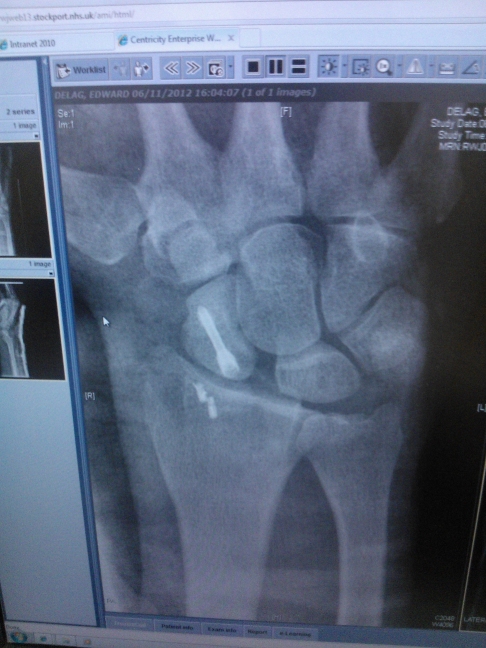

I had an almost identical break to the one you have posted.

The surgeon reckons that coz I did my radius and dislocated my perilunate as well as split my scaph in two that I shouldn't ride until February.

Listen to the surgeon then. Too much movement or impact may cause problems such as non-union of the scaphoid and possible avascular necrosis which is a far bigger problem...